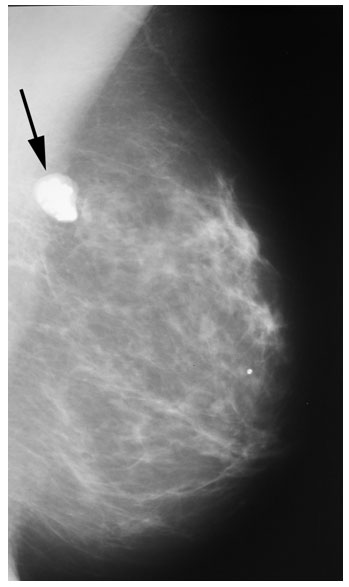

Диагностировать липому может врач хирург после визуального осмотра и пальпации места новообразования. По рекомендации врача может потребоваться УЗИ мягких тканей, маммография или биопсия с цитологическим или гистологическим исследованием.

По рекомендации врача может потребоваться УЗИ мягких тканей, маммография или биопсия с цитологическим или гистологическим исследованием.